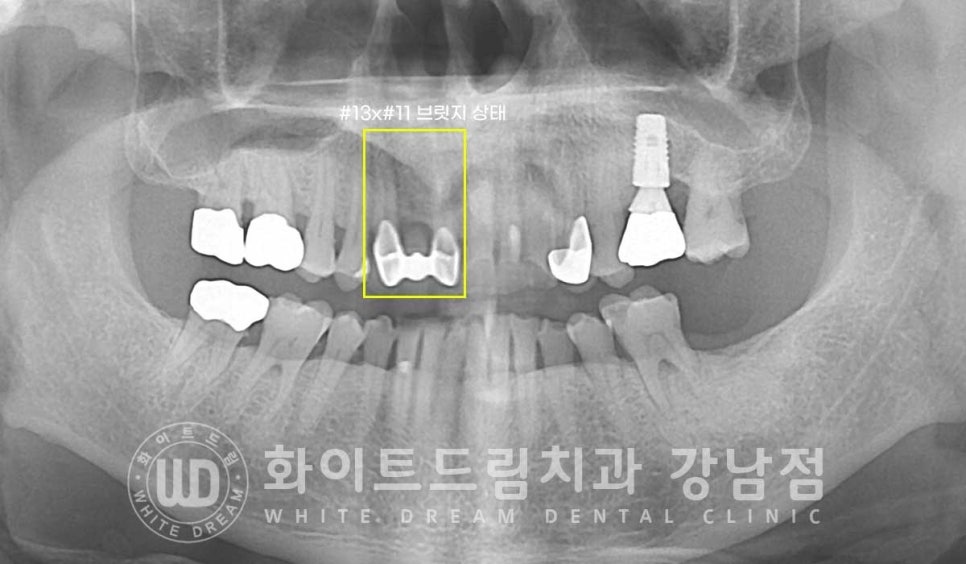

전치부 중 11번부터 13번 치아는 브릿지로 치료를 받으신 상태입니다.

브릿지와 옆 인접치들의 치아 색상과 모양이 달라 이질감이 심해 보여요.

통일성 있게 치아라인을 만들어주세요.

치료를 원하시는 21, 22, 23번 치아를 자세히 보면

21번 치아는 치경부 충치가 있는 상태이고

22번 치아는 기존에 gi로 치료받은 부위 하방으로 충치가 발생한 상태

23번 치아는 치경부마모로 내부 상아질이 노출되어 있는 상태입니다.